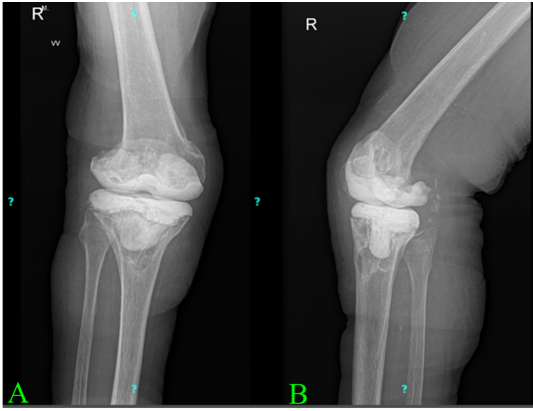

According to the 2018 International Consensus Meeting criteria, the presence of a sinus tract constitutes a major criterion for PJI. Consequently, the first stage of the planned two-stage revision was performed ahead of schedule. In January 2025, the infected prosthesis was explanted, and an antibiotic (vancomycin and gentamycin) elution handmade bone cement mobile spacer was implanted. Follow-up radiographs taken 6 weeks postoperatively are shown in Fig. 4.

Figure 4: Anteroposterior and lateral radiographs of the right knee following spacer implantation, taken 6 weeks postoperatively. The image in panel A (a) shows the anteroposterior view, and image in panel B (b) shows the lateral view.